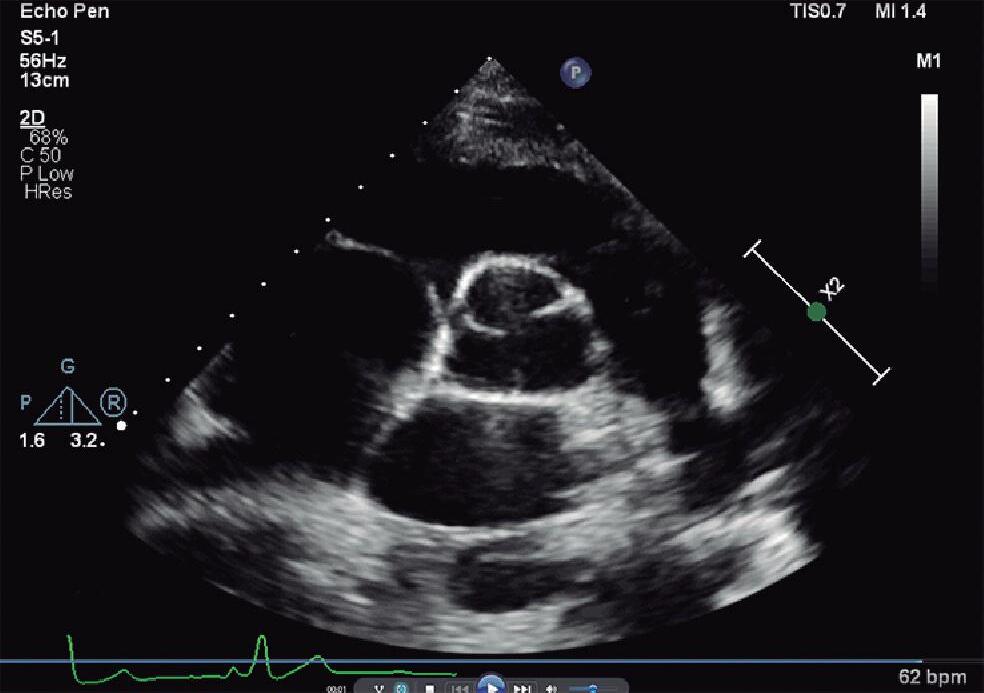

Para obter o plano paraesternal eixo curto, “rodamos” o transdutor no sentido horário com o index apontando para o ombro esquerdo do paciente (▶ Vídeos 1-17 e 1-18). A visão eixo curto das grandes artérias consiste em valva aórtica (posicionada no centro da imagem), via de saída do VD (região infundibulovalvar do VD e artéria pulmonar), valva tricúspide e átrios (Fig. 1-7a e ▶ Vídeo 1-19). Movimentando o transdutor no sentido craniocaudal também é possível obtermos o eixo curto dos ventrículos ao nível dos músculos papilares e da valva mitral para a análise da contratilidade ventricular, do septo interventricular muscular e da valva mitral (Figs. 1-5b e 1-7b, c; ▶ Vídeos 1-17, 1-18, 1-20 e 1-21). O mapeamento em cores é importante para pesquisa de comunicação interventricular muscular e disfunção valvar mitral (Fig. 1-7).

Fig. 1-7. Plano paraesternal eixo curto com Doppler colorido: grandes artérias (a), eixo curto dos ventrículos ao nível dos músculos papilares (b) e da valva mitral (c). AD: átrio direito; AE: átrio esquerdo; VD: ventrículo direito; Ao: aorta; AP: artéria pulmonar; VT; valva tricúspide; VP: valva pulmonar; VE: ventrículo esquerdo; S: septo interventricular; mp: músculo papilar; VM: valva mitral.